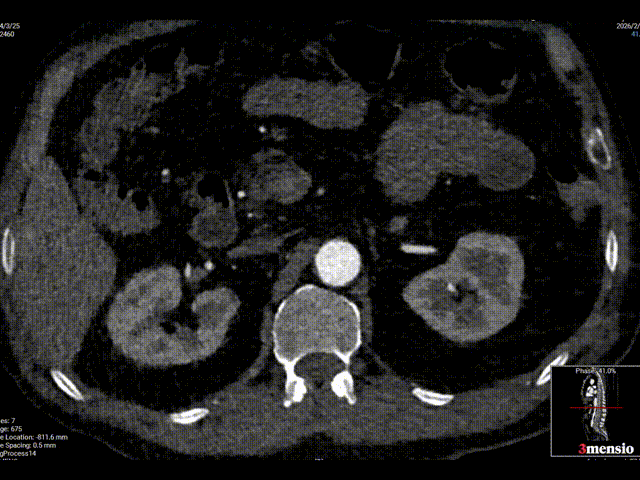

术前影像学诊断结果:腹主动脉穿通性溃疡伴假性动脉瘤形成。

腹主动脉末端壁间血肿伴局部穿通性溃疡,肠系膜下动脉粗大。